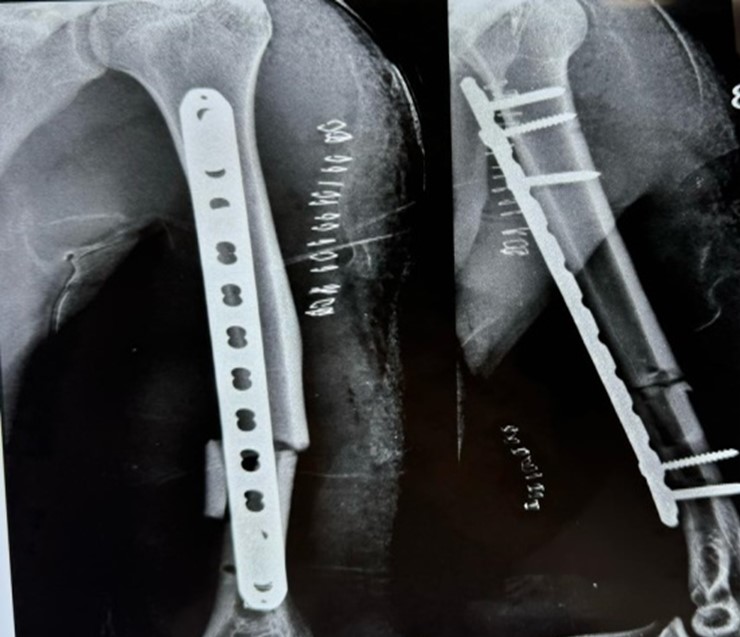

35 year old male patient suffering from closed displaced diaphyseal humerus fracture without distal neurovascular deficit. Follow up was taken at 3months post operatively and 12 months post operatively

Immediate post operative xray